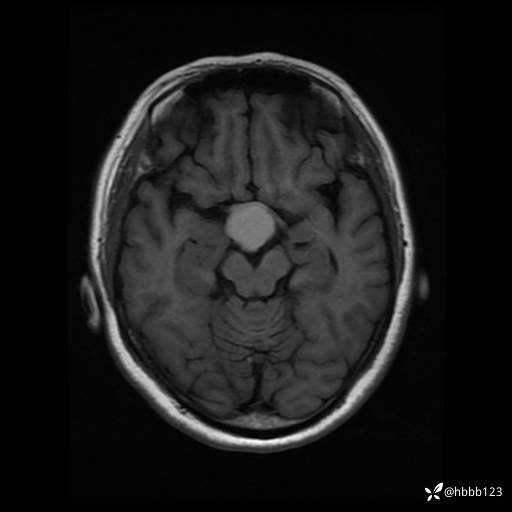

T1WI: